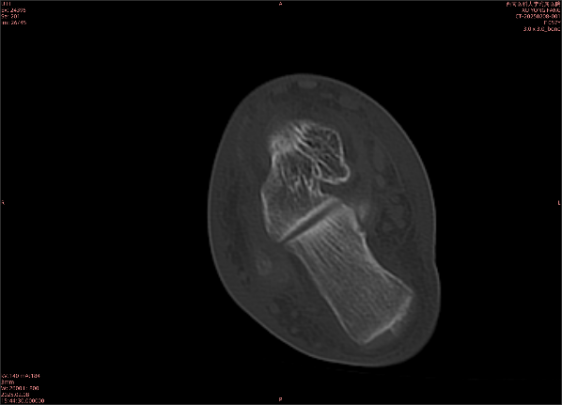

举例图像

图1

专业解释看不懂没关系,大家看图1和图2就可以了,这是同一个患者跟骨的磁共振和CT图像,图1的红色箭头指示的黑线就是磁共振图像显示的骨折线,一目了然。而对比图2的CT图像上并未显示异常。